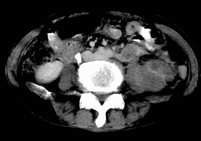

病患,女,69岁,左侧腰部不适,偶感疼痛2个月余,无化验室检查,行彩超发现左侧肾区实质性肿物,后行ct检查,结果同上。

左肾不规则软组织肿块,内见低密度坏死区,与正常肾实质分界不清,左肾明显增大,增强呈不规则条索状强化,肾盂及左输尿管上段扩张。肾周脂肪层受侵、模糊。印象:典型左肾癌。

平扫,表现为肾实质肿块,呈分叶状,肿块密度不均,内有不规则低密度区(陈旧性出血?坏死?)有的似呈囊性,增强明显不均一强化,与肾实质相比呈相对低密度的不均一肿块,肾周脂肪间隙可见,肾前筋膜未见增后,肾血管及腹主动脉旁未见肿大淋巴结影

左侧肾癌并肾静脉癌栓.腹膜后淋巴结肿大转移.

三期抓的不错,典型的肾癌,且已累及肾盂及左输尿管上段

左肾癌累及左输尿管,左肾静脉无受累征象。